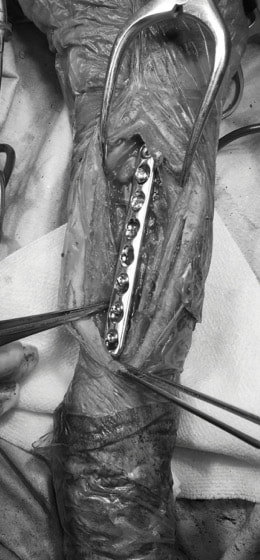

Advanced Locking plate system と Locking compression plate system

当院ではAdvanced Locking plate system(ALPS)と、Locking compression plate system(LCPS)という骨接合法で骨折症例の治療を行っています。

Advanced Locking Plate System

従来型のプレートのように広い面積で骨と接するプレートを用いて固定を行った場合、プレート下の骨はプレートとの接触面において血行が絶たれ壊死し、それがリモデリングされると骨密度が低下する。この骨密度の低下防ぐために、骨折部局所への血行を温存することの重要性が近年改めて認識されるようになってきている。Advaed Locking Plate System (ALPS)は従来型のプレートシステムの欠点を改良し、より使いやすく、より骨への血行を阻害しないようにというコンセプトで作られた。

Advanced Locking Plate System の特徴

- 骨への血行障害は最小限である

- 上下左右にベンディング可能でより3次元的な成形が可能

- すべての部位においてプレート強度は均一である

- ロッキングスクリューと圧着型スクリュー(皮質骨スクリュー)の双方が使用できる

- ダイナミックコンプレッション機能

- 生体親和性の高いチタン製

- トイ犬種から馬まで応用できるサイズ展開がある

トイプードル 右遠位橈尺骨短斜骨折のALPSによる内固定

Locking Compression Plate

LCPは、スクリュー(ネジ)とプレート(金属の板)をロックする特殊な構造により骨折部位を固定する新しい世代のプレートシステムです。ひとつのホールでロッキングスクリューとスタンダードスクリューの使用を選択できるユニークな構造をしているため、骨折断端間の圧迫を目的とした従来型プレート固定法に加え、高い角度安定性を有するロッキングスクリューを用いた固定法の選択が可能です。従来のプレートシステムでは困難だった部分の骨折や癒合不全の症例に高い治療効果をもたらします。